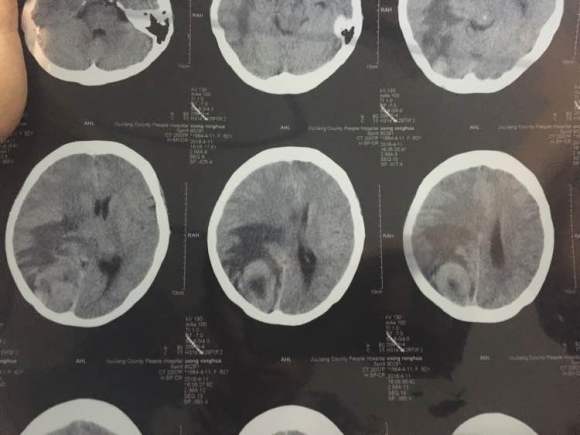

我婆婆两年前查出肺癌早期,切除两片肺叶,一个月前出现头疼,昨天拍了片子,医生说情况不太好,我这里三四线城市,现在劝她...